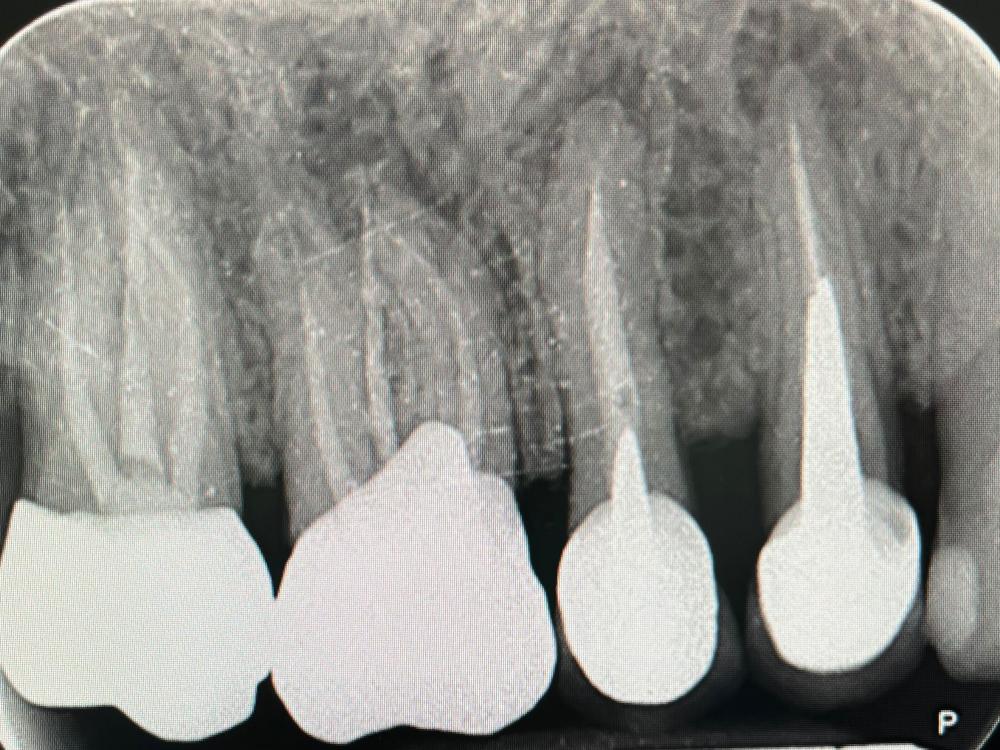

Presso lo Studio Dentistico Zambon siamo specializzati in trattamenti avanzati come il postestrattivo con carico immediato, un intervento innovativo che consente di sostituire i denti mancanti in modo rapido e sicuro, riducendo notevolmente il tempo di guarigione e il disagio per il paziente.

Grazie all’utilizzo della chirurgia guidata, siamo in grado di pianificare e realizzare impianti dentali con precisione, assicurando risultati eccellenti e duraturi.

Il trattamento postestrattivo con carico immediato è un protocollo che permette di inserire un impianto dentale subito dopo l’estrazione del dente naturale, evitando lunghi tempi di attesa tra l’estrazione e l’inserimento del nuovo dente. Questa soluzione si dimostra ideale per chi desidera ripristinare il sorriso e la funzionalità dei denti in tempi ridotti, evitando multiple sedute e massimizzando il comfort.

La chirurgia guidata è una tecnica avanzata che si avvale di tecnologie digitali per pianificare e simulare l’intervento in modo personalizzato. Con una scansione digitale 3D della bocca, il nostro team può posizionare gli impianti con estrema precisione, seguendo un percorso predefinito che riduce il margine d'errore. Questo approccio, unito al trattamento postestrattivo con carico immediato, offre diversi vantaggi: